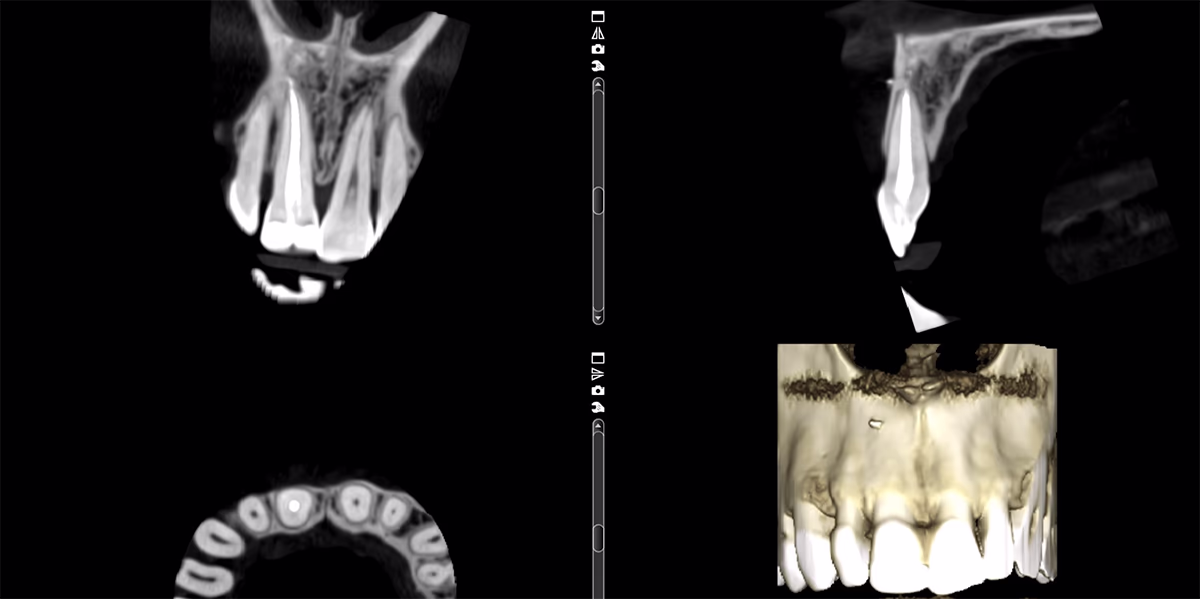

Зуб 11 із раніше виконаною композитною реставрацією. В анамнезі – ендодонтичне лікування понад 5 років тому. Зуб відновлений із застосуванням скловолоконної штифто вої конструкції та композиту.

За даними КТ: кореневий канал обтурований гомогенно до апекса, ознак апікальних змін немає. Одиничну кишеню не виявлено. Стан тканин пародонта – у межах норми.